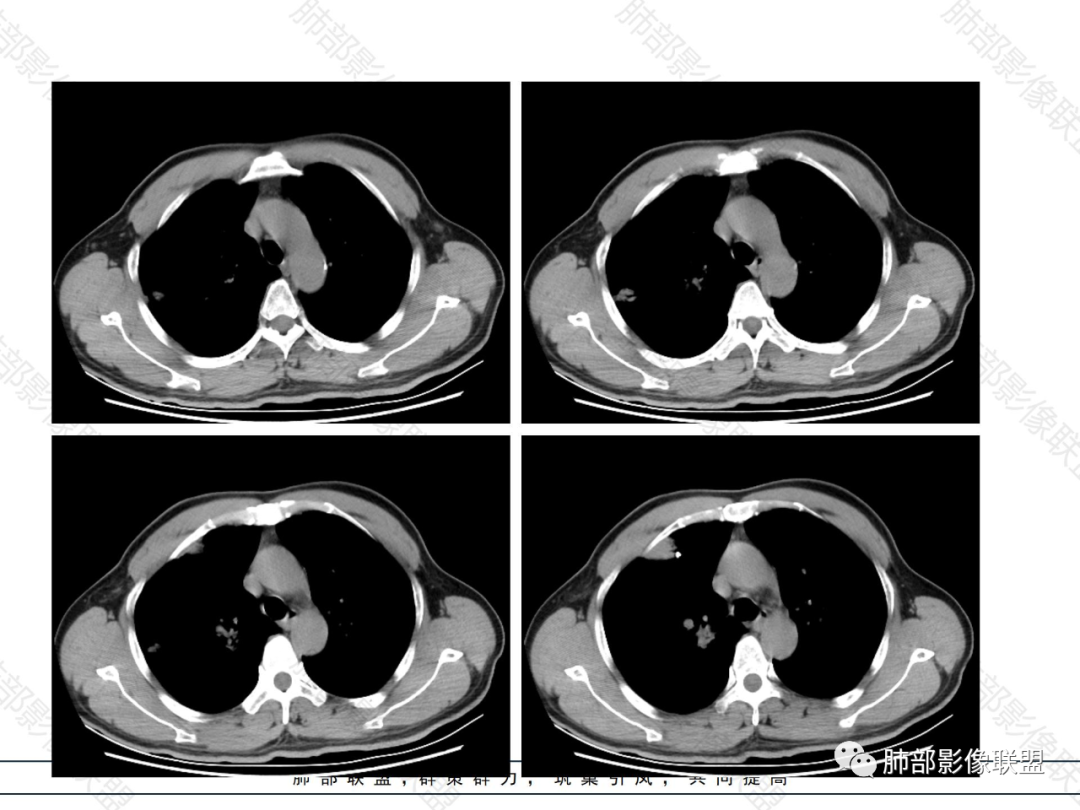

胸膜下多发实变病灶

外围胸膜下、支气管血管束分布

实变,密度较均匀

病灶的边缘平直、膨隆都有

内部支气管稍扩张,直达远端,或受压变形、移位

均匀强化

内部血管走形自然,稍纤细

1.病灶分布:因为肺内淋巴瘤主要侵犯对象是肺间质和支气管黏膜下组织,病灶主要位于在沿支气管血管束分布、肺间质及胸膜下,病灶可跨叶分布。

2.病灶的密度:密度均匀,部分病灶内可见空洞及气液平,轻中度均匀强化。

5.病灶的边缘:有膨隆,浅分叶,也有平直、收缩,平直收缩是因为肿瘤组织浸润致肺泡塌陷及周围纤维组织增生,牵拉正常的肺组织向病灶中心形成聚拢状改变,似呈“炎性”改变。

膨隆、平直